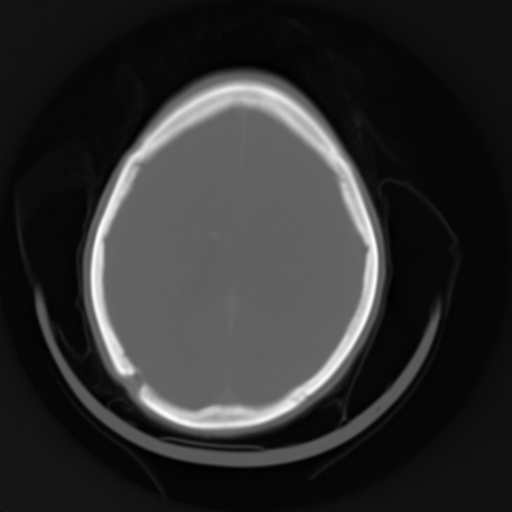

By taking a lot of X-ray images at a range of angles around the body, one can create a three-dimensional reconstruction of the anatomy. This process is known as Computed Tomography or CT (also known as Computed Axial Tomography or CAT scans--the "axial" and the "A" are often left off these days).

brainthorax

CT image examples

Notice that the image slices across the axis of the body instead of projecting through it.